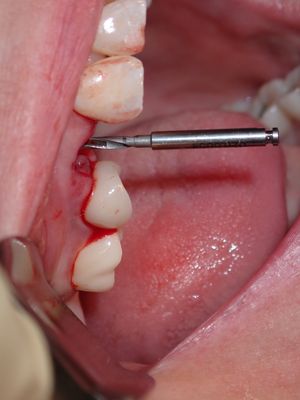

relatively straight forward immediate placement, loss of labial plate at apex of 3mm, implant placed well away from that site, grafted that region from internal of socket with membrane and bone prior to placing implant. additional bone placed post implant placement .